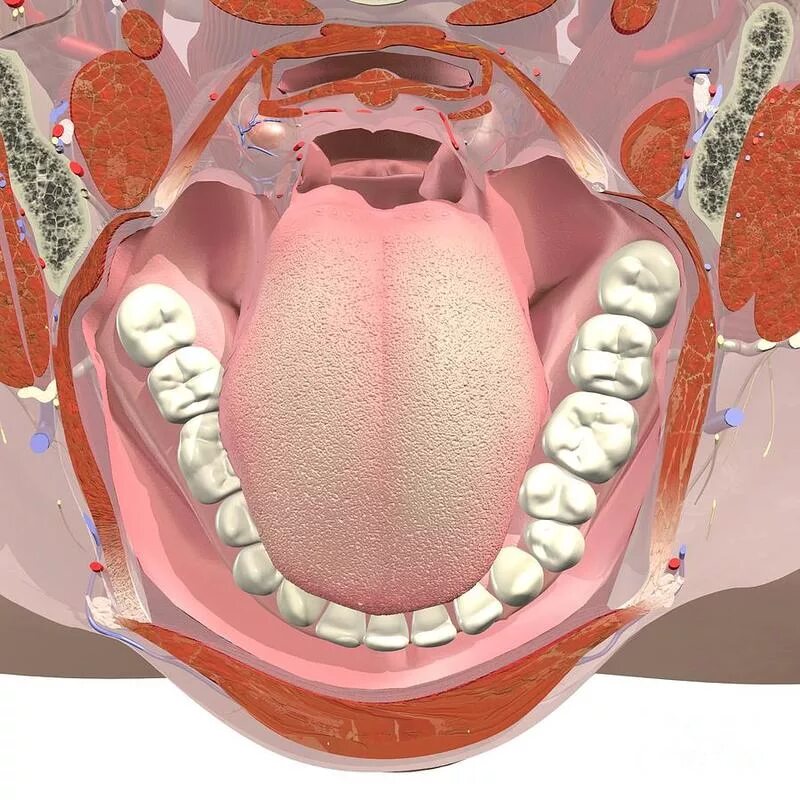

Снимок ротовой полости